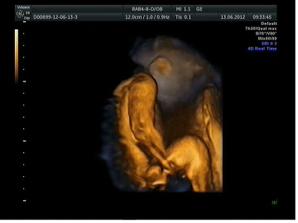

13.6. 3D ultrazvuk - miminko je stydlín, nechtěl nám ukázat hlavičku, pořád si ji schovával 🙂 Odhad váhy dle měření 765 g, 24+5 a předpokládaný termín porodu 28.9.2012, opět potvrzen chlapeček - tentokrát to viděla i maminka s tatínkem 🙂